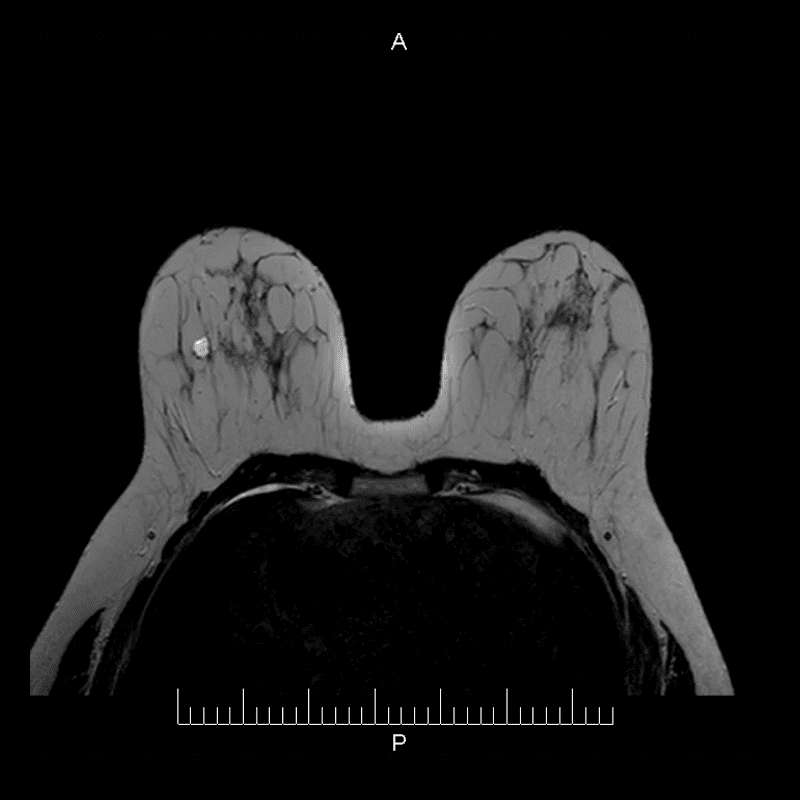

La paciente se recuesta sobre la mesa del equipo RM, ambos senos son posicionados sobre una antena especial, la cual adquiere las imágenes.

Primero se toman imágenes sin la sustancia de contraste.

Una inyección intravenosa de sustancia de contraste (gadolinio) se aplica a la paciente.

Se adquieren las imágenes de perfusión (con contraste).

Ambas imágenes son comparadas.